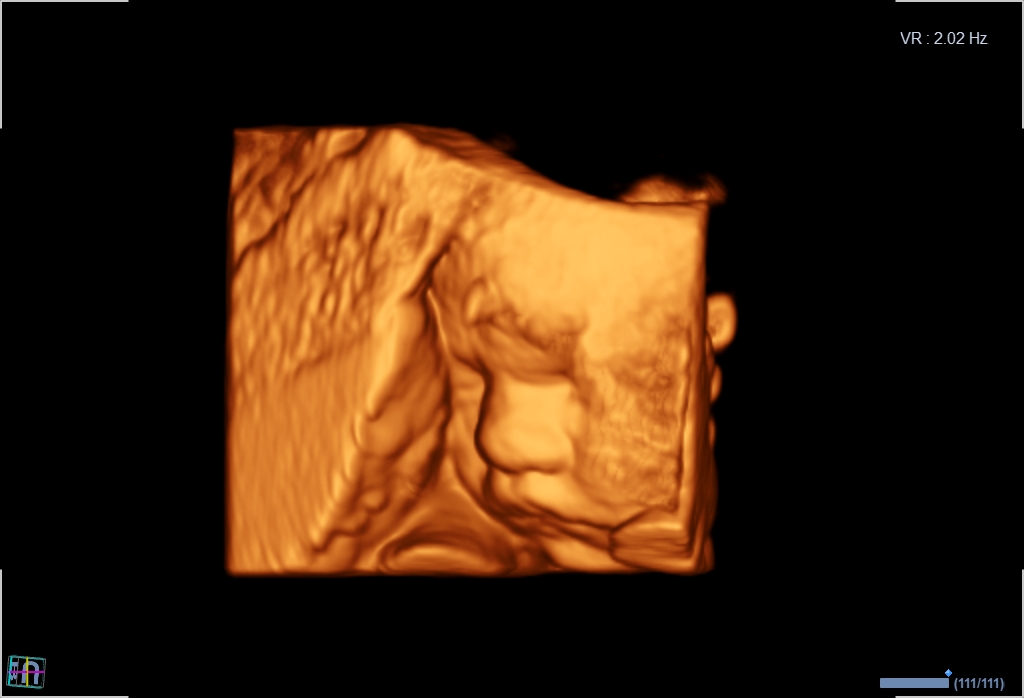

Seit März 2019 steht ein neues 3D/4D-Ultraschallgerät für faszinierende Eindrücke von Ihrem Baby zur Verfügung.

Außer den Fotos können auch 3D/4D Viedeoclips gemacht und auf einem USB-Stick gespeichert werden. So können die Bilder und Clips jederzeit angesehen werden.